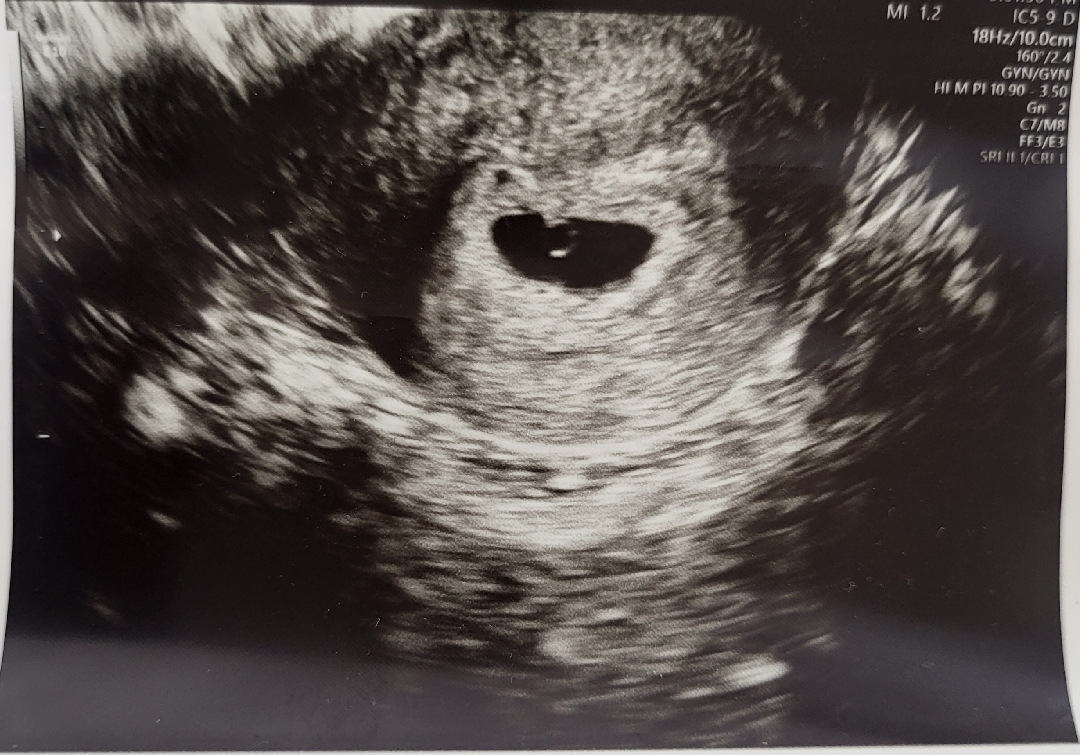

시험관으로 얻은 첫임신중에 갑자기 생리하는것처럼 배가 아프고 출혈에 놀라서 병원에 가서 초음파 했는데 잘있다고하네요 처음 초음파였는데 초음파 사진받고 안심이 되서 그런가 눈물이 하염없이 나왔어요ㅠㅠ 일단 아스피린이랑 배주사 질정은 중단하고 출혈멈출때까지 엉덩이 주사 맞다가 안멈추면 병원에 방문하라고 하네요ㅠㅠ 지금 의사소견으로는 피고임이 약간있다고 해서 안정을 취하라고 하네요ㅠㅠ